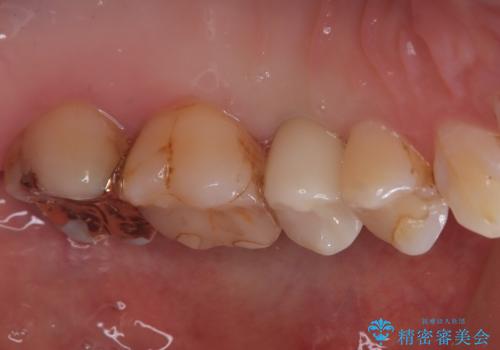

今回の症例では、骨の量が十分あったため、比較的短期間で治療を完了することができました。インプラントを使用することで、安定した咬み合わせが実現し、患者様は痛みもなく安心して食事を楽しむことができるようになりました。

インプラント治療は、しっかりとした診断と計画のもとに行われることで、自然な見た目と快適な噛み心地を取り戻すことができます。もし、歯を失ってお困りの方や、他の治療法で満足していない方がいらっしゃいましたら、ぜひ一度ご相談ください。